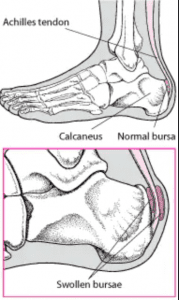

The Signs of Achilles Tendinitis Sydney Heel Pain hot sale, Achilles tendon injuries healthdirect hot sale, Back of Achilles Tendon Heel Pain Shoes Orthotics Home Treatment hot sale, Know the Symptoms of Achilles Tendonitis Tendinopathy Gait Happens hot sale, Back of Achilles Tendon Heel Pain Shoes Orthotics Home Treatment hot sale, Chronic Achilles Tendon Pain Diagnosis Treatment HSS hot sale, Achilles Tendinitis Symptoms Treatment hot sale, Heel Pain Causes Treatment and Prevention hot sale, Achilles Tendinitis Ankle Pain Foot Injury hot sale, Pain at the back of the heel The BMJ hot sale, Pain at the back of the heel How to figure out what s causing it and what to do about it hot sale, Achilles Tendon Injuries Johns Hopkins Medicine hot sale, Achilles Tendonitis Treatment in Gilbert Scottsdale Chandler Mesa Phoenix hot sale, Achilles Tendinitis in Children Causes and Treatment hot sale, Achilles Tendon Pain Symptoms Causes Treatment Exercises hot sale, Achilles Tendonitis Causes Symptoms Signs Gleneagles Hospital hot sale, HealthCrib THE FOOT Achilles tendinitis is a form of inflammation seen within the tendon of the calf muscle group gastrocnemius and soleus Typically seen in runners brought on by a hot sale, Why You Should Never Ignore Achilles Heel Painv Suncoast Orthopaedic Institute hot sale, Protecting Your Achilles Heel From Injury Dr Gordon Slater hot sale, Back of Achilles Tendon Heel Pain Shoes Orthotics Home Treatment hot sale, Home Remedies for Achilles Tendinitis Cornerstone Foot Ankle hot sale, Shooting pain store up achilles tendon hot sale, Achilles tendinitis Information Mount Sinai New York hot sale, Keeping Up Your Routine With Achilles Tendonitis Precision Foot and Ankle hot sale, Achilles Tendon Rupture Brisbane Physiotherapy hot sale, Pain In The Back Of The Heel What Could It Mean hot sale, How to Relieve Achilles Tendonitis in SECONDS hot sale, Achilles tendon rupture Wikipedia hot sale, Physiotherapy for Achilles Tendonitis Complete Care Physiotherapy Centre hot sale, Achilles Tendonitis Treatment in Gilbert Scottsdale Chandler Mesa Phoenix hot sale, Achilles Tendon Pain Symptoms Causes Treatment Exercises hot sale, Pain in the Back of the Heel Causes and Treatment hot sale, When to Worry About Calf Pain Causes and Warning Signs hot sale, Heel Pain Signs and Symptoms of Achilles Tendonitis Podiatrist in Walnut Creek hot sale, Achilles Pain While Running What It Means and What to Do hot sale.